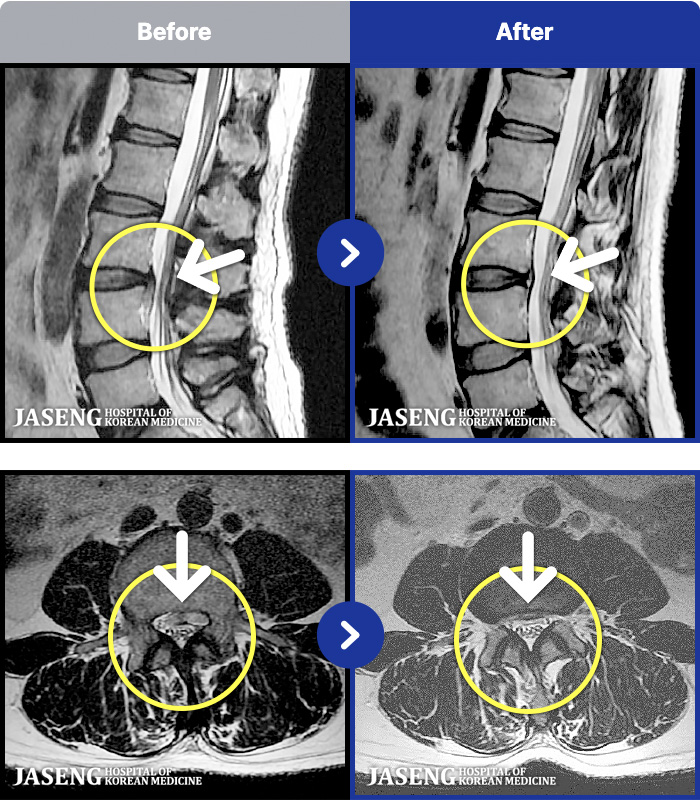

MRI ġ

1,301 MRI ũ ʸ Ȯϼ.